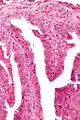

Micrograph of a papillary hidradenoma with papillary structures; fragmented overlying epidermis is at the top of the image. H&E stain.

Microscopic histopathological analyses of papillary hidradenoma tumors typically reveal a nodule in the dermis, i.e. layer of skin between the epidermis and subcutaneous tissue. The tumor consists of complex patterns of interconnecting tubular and papillary (i.e. thin finger-like or frond-like) structures.[19] These structures are lined with glandular epithelial and myoepithelial cells. The glandular epithelial cells appear to be excessively proliferating in the ducts leading to the epidermis and show oxyphilic changes, (i.e. cytoplasm filled with large mitochondria, glycogen, and ribosomes) while the myoepithelial cells often appear clear cell-like, i.e. have uncolored cytoplasm when stained with hematoxylin and eosin.[1] The histopathology of anogenital and ectopic papillary hidradenomas are similar to each other.[7][9][15][18]